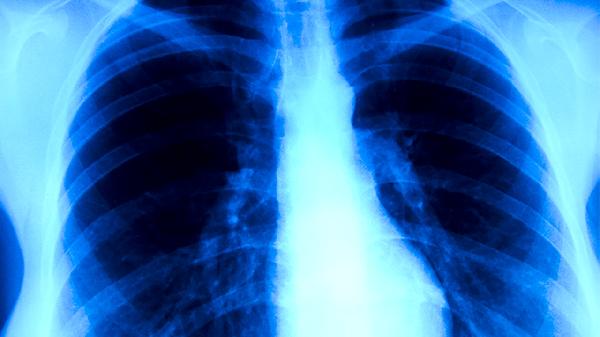

肺炎衣原体检测阴性后仍出现进行性呼吸困难、持续高热等症状,可能与标本采集不规范、检测窗口期或技术局限性有关。免疫功能低下者可能出现不典型表现,需通过胸部影像学检查评估肺部病变。重复检测或联合多种检测方法有助于明确诊断误差。